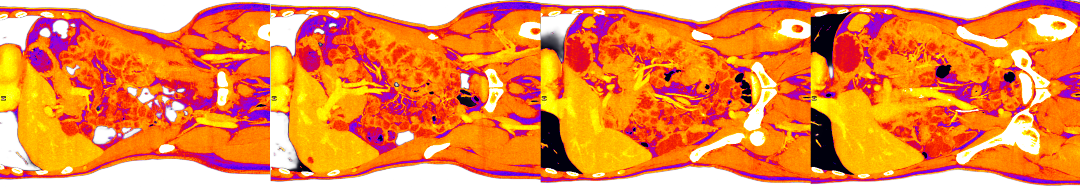

This post concerns an impending death; my own. My recent diagnosis (Mar 4ᵗʰ) is both complicated, but also typical of a stage four lung cancer (metastatic cancer), if I understand it right, with the cancer identifying itself only weeks ago, and further growths identified since then: I have tumours in the legs, lymph nodes and adrenal glands; a 4.5 cm tumour on the left lung is crowding out the nearby aorta; it has sprouted a smaller (11 mm) tumour on the right lung too; and colonies have set up camp in the cerebellum. A round of CT (Computed Tomography), MRI (Magnetic Resonance Imaging), X-Ray, EBUS (Endobronchial Ultrasound), and PET (Positron Emission Tomography) scan results is still being analysed. New facts emerge. I’m only just weeks into things and counting.

A PET scan is organised a few days later, at St Barts Hospital, in the shadow of St Paul’s. The body is flooded with a tracer radioactive fluid, after which you are locked into a lead-lined box for three-quarters of an hour to allow it to bake in. The scanner then detects where the tracer has been absorbed by cell growth anywhere in the body it is directed, producing reams of flowing light captured to film, copies of which—scans of my own body—are used throughout this post.

On seeing further scans, I recognised, eg., my rib cage as something indeed very much like the frame of Israel’s tents (above, top left), beaming on the shore of the infinite (Blake), but also, in the twisting images of the torso, I am struck by the sprawling energies at play, unleashed by disease. No longer is there the assumed underlying durable person, sealed away from the totality, cybernetically establishing their personal border by fending off and repurposing the chaos, sickness and disorder without. Instead, raw energies start to coalesce, turning Urizenic, mechanical rigidity into flashes, streaks and pulses of contending light.

When looking at the flowing lights of the scans, I am not seeing the regular mechanics/dynamics of fluid flow and the like. It is not the competing power of the different forces involved, sloshing against one another, that impresses. That would represent a reasonable romantic regard for the power of things we don’t fully understand, and which we dimly suspect may outbid us in the end.

What I find more compelling in the forms on show are the signs of a deeper, primordial language of the cosmos, God’s being and the unconstrained underpinning of all those other things, the syntax of God’s mind and its reality of eternal esemplatic (form-giving, creative) inflation. To see the churning faces of the sea of light is to see the surface of the esemplasm that is all being, and which calls us from its depths.